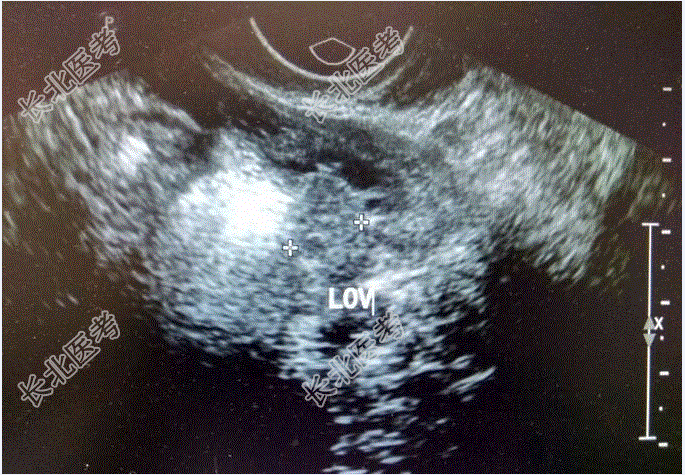

查β-HCG>150000mIU/ml;彩超提示:1、侵袭性葡萄胎待排2、子宫内膜增厚伴宫腔积液3、宫颈肥大伴回声欠均匀4、盆腔积液;2023-1-27外院胸部CT提示:1、两肺多发小结节,考虑转移。再次于行清宫术,术后血HCG下降:160000mIU/ml,术后病理示:镜下见蜕膜、出血、坏死组织中见细胞滋养叶细胞及合体滋养叶细胞。滋养叶细胞增生伴轻度异型,未见确切绒毛结构。患者自诉此次清宫术后血HCG一度下降至50000mIU/ml左右,后复查HCG再次上升至β-HCG:89000mIU/ml。外院会诊后考虑为“绒癌”并于予5Fu1.5静滴8小时d1-8,放线菌素-D0.4mg静滴d1-8化疗。化疗后:β-HCG91000mIU/ml,2023-4-1:β-HCG:90000mIU/ml,2023-4-1外院CT提示胸部多发转移灶较前增大。遂于2017-4-14至我院就诊住院治疗,2023-04-20起给予5-Fu+KSM方案化疗:5-FU(1.5gd1-d4,1.75gd5-d8)+KSM(200μgd1,400μgd2-d8),观察无明显化疗副反应。2023-5-6于外院复查血常规正常,β-HCG2597.36mIU/mL。第二次化疗后至今患者无咳嗽咳痰,恶心呕吐,腹痛腹泻等不适症状。现患者为求进一步诊治,门诊拟“恶性葡萄胎”收治入院。

既往史:患者于25岁时足月顺产一健康活婴;于35岁时足月剖宫产一健康活婴;剖宫产后10月因“葡萄胎”行清宫术3次;2015-02-05再次于外院行清宫术。已婚,2-0-3-2,患者于25岁时足月顺产一健康活婴;于35岁时足月剖宫产一健康活婴。15岁,月经规律,4-5/40,量中,痛经(-),闭经4年。查体:T:36.9℃,P:88次/分,R:18次/分,BP:140/90/mmHg。妇科检查:外阴:(-);阴道:通畅;宫颈:光滑;子宫:前位,增大如孕8周,活动可。双附件(-)。辅助检查:胸片:两肺多个结节影,拟转移瘤,两肺纹理增多,主动脉迂曲。血常规:白细胞计数7.30×10⁹/L,血红蛋白125g/L,血小板计数405↑×10⁹/L。